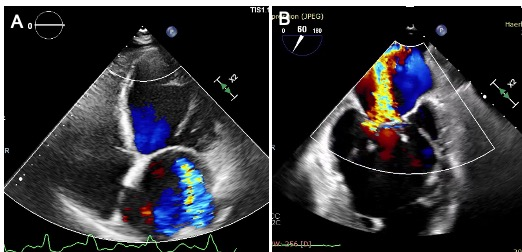

术前经胸和食道超声结果。左图:经胸超声提示心房心室扩大,二尖瓣重度反流;右图:食道超声提示二尖瓣重度反流(彩色血流)。

家住黑龙江省黑河市,今年71岁的王大爷(化姓)两年前出现了活动后呼吸困难的症状,休息后有所缓解,在此其间反复就诊于当地医院,但内科保守治疗均无效,症状没有缓解。一个月前王大爷呼吸困难加重,心悸、乏力,无法平卧,情况危急,家人立即将其送至ac米兰官网中文网站二院。经检查确诊为心功能不全,二尖瓣重度反流,左心室舒张末内径显着扩大至68 mm,LVEF(心脏射血分数)降低为38%,心衰标志物NT-proBNP高达23072 pg/ml。经过规范的一个月的抗心衰药物治疗后,患者的症状仍未缓解,而且本次入院后超声提示LVEF为32%,二尖瓣仍为重度反流。但该患者已年逾七旬、体质弱、心功能差,属传统外科开胸手术高危人群。